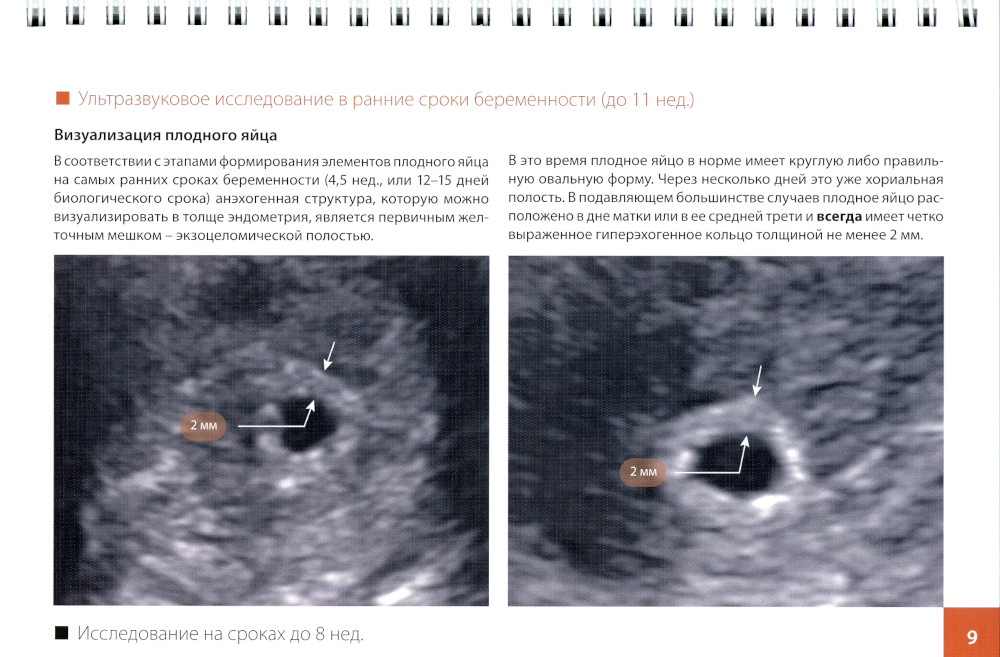

В книге обсуждаются возможности ультразвуковой визуализации различных структур плодного яйца в процессе нормальной маточной беременности, приводятся признаки неблагополучия на всех этапах ее развития, демонстрируются возможности ультразвуковой диагностики некоторых врожденных аномалий в эмбриональном периоде, представлены рекомендуемые протоколы исследования. Описаны основные анатомические структуры, доступные для оценки на сроках беременности 11-14 нед., определены оптимальные сроки проведения исследования. Представлен оптимальный алгоритм оценки ультразвуковой топографической анатомии, включая маркеры хромосомных аномалий. Пособие предназначено для врачей ультразвуковой диагностики, специалистов пренатальной диагностики, акушеров-гинекологов, перинатологов, а также студентов и ординаторов медицинских вузов.| Издательство | МЕДпресс-информ |